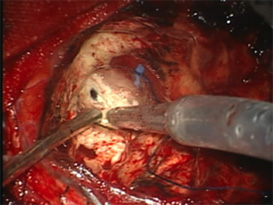

蛍光診断(光線診断) PhotoDiagnosis(PD)

脳腫瘍、特に神経膠腫(glioma)では摘出術中に正常の脳組織との区別が難しいことがしばしばあります。そのような場合には、脳腫瘍かと思って切除したら大事な正常脳組織であったり、また正常組織かと思われた部分が脳腫瘍の一部であるということが術後のMRI検査でわかるということもあります。これを防ぐために用いられる方法が蛍光診断です。

手術前にアミノレブリン酸というお薬をブドウ糖に溶かして内服していただきます。そして手術中に脳腫瘍のあたりに青い光を当てると腫瘍だけが赤く光って見えます。

(左図)腫瘍を摘出後

(右図)青い光を当て、残存腫瘍だけが赤く光る。

この赤く光った部分を摘出すれば腫瘍の全摘出が完了します。